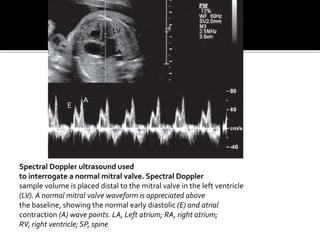

Spectral Doppler ultrasound used

to interrogate a normal mitral valve. Spectral Doppler

sample volume is placed distal to the mitral valve in the left ventricle

(LV). A normal mitral valve waveform is appreciated above

the baseline, showing the normal early diastolic (E) and atrial

contraction (A) wave points. LA, Left atrium; RA, right atrium;

RV, right ventricle; SP, spine

Spectral Doppler ultrasoundused to interrogate a normal mitral valve. Spectral Doppler sample volume is placed distal to the mitral valve in the left ventricle (LV). A normal mitral valve waveform is appreciated above the baseline, showing the normal early diastolic (E) and atrial contraction (A) wave points. LA, Left atrium; RA, right atrium; RV, right ventricle; SP, spine RV LV RA LA E A